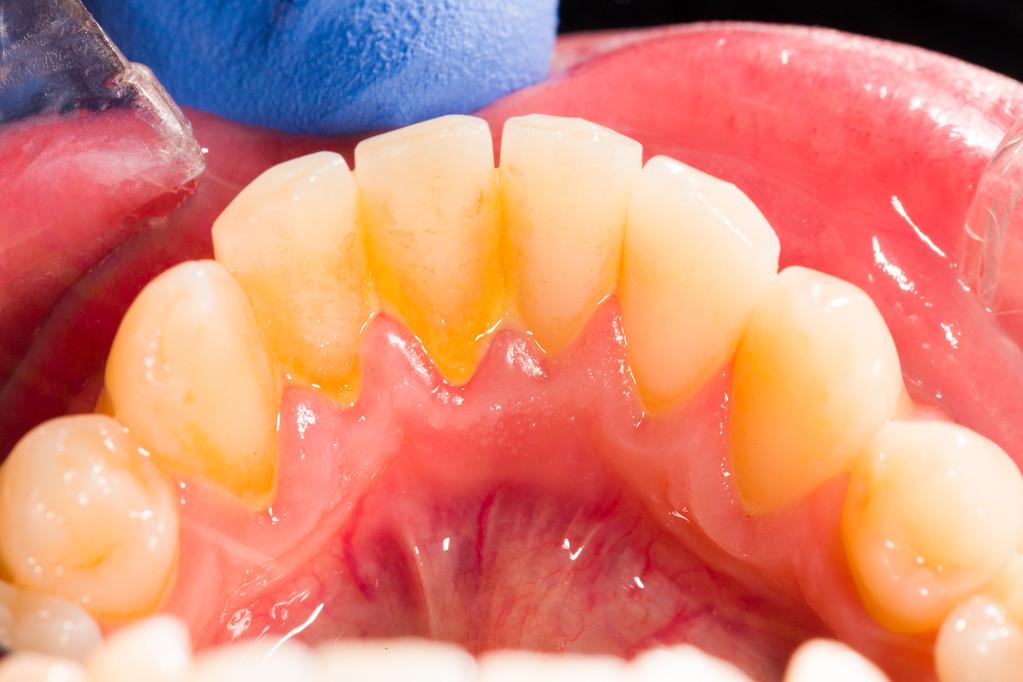

牙齦炎是一種牙齦發炎的情況,其主要特徵是在刷牙或使用牙線時容易出血,其他症狀包括牙齦發紅、腫脹,口中可能有異味,牙齦之間可能有膿液,牙齒的咬合改變,牙齒之間可能出現間隙,部分假牙可能不合適,以及牙齒可能鬆動或脫落。

牙齦炎的形成是由於食物殘渣、唾液和細菌混合形成的牙菌膜附著在牙齒表面上。如果不使用牙膏刷牙和使用牙線清除牙菌膜,它將變成堅硬的牙石,只有專業的洗牙才能將其清除。

牙菌膜和牙石中含有有害細菌,如果它們沒有清除,就會刺激牙齦並引起牙齦炎。